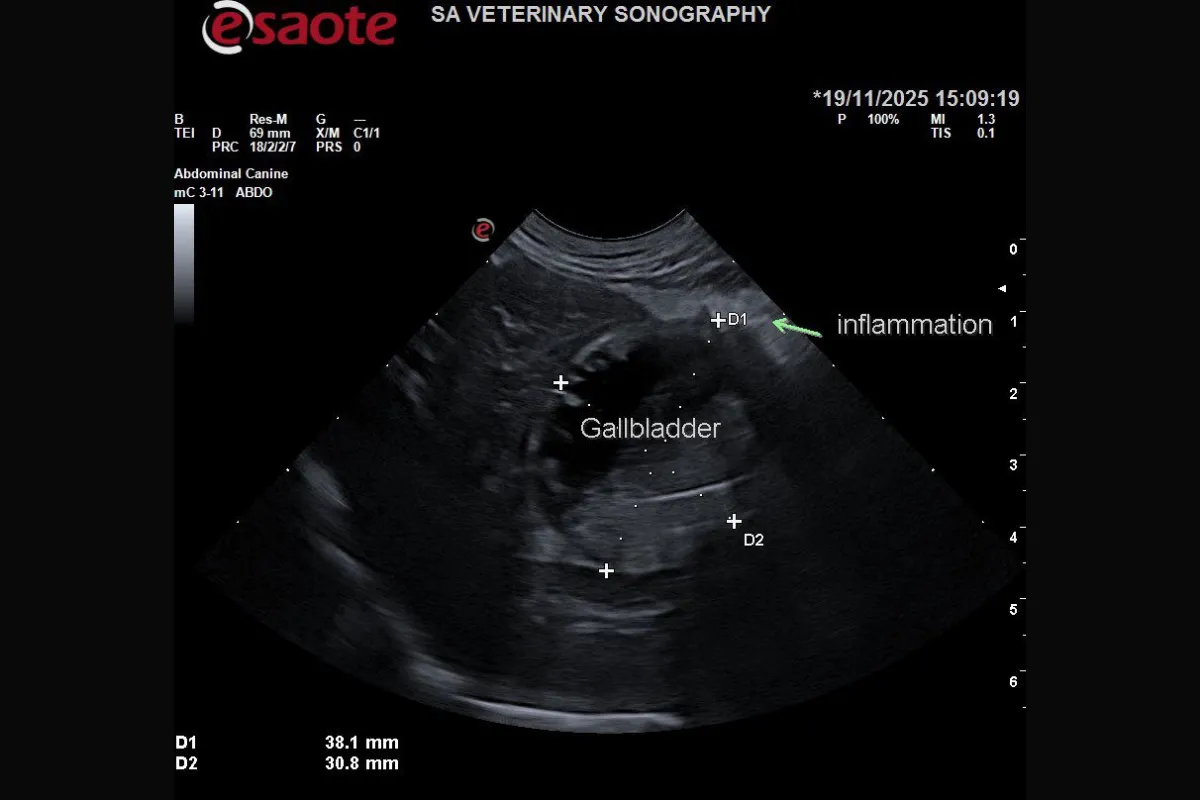

Ultrasound revealed extensive inflammation in the cranial abdomen, with hyperechoic, hazy fat and reduced acoustic detail. A small volume of echogenic effusion surrounded the area.

The gallbladder was severely abnormal: distended, thick-walled, and containing a mix of organised and motile sludge. Significantly, a gas artefact was visible arising from the gallbladder wall, an alarming finding consistent with emphysematous cholecystitis, a life-threatening infection that risks rupture and fatal peritonitis. Adjacent to the gallbladder, a poorly defined hypoechoic lesion within the liver suggested a possible abscess.